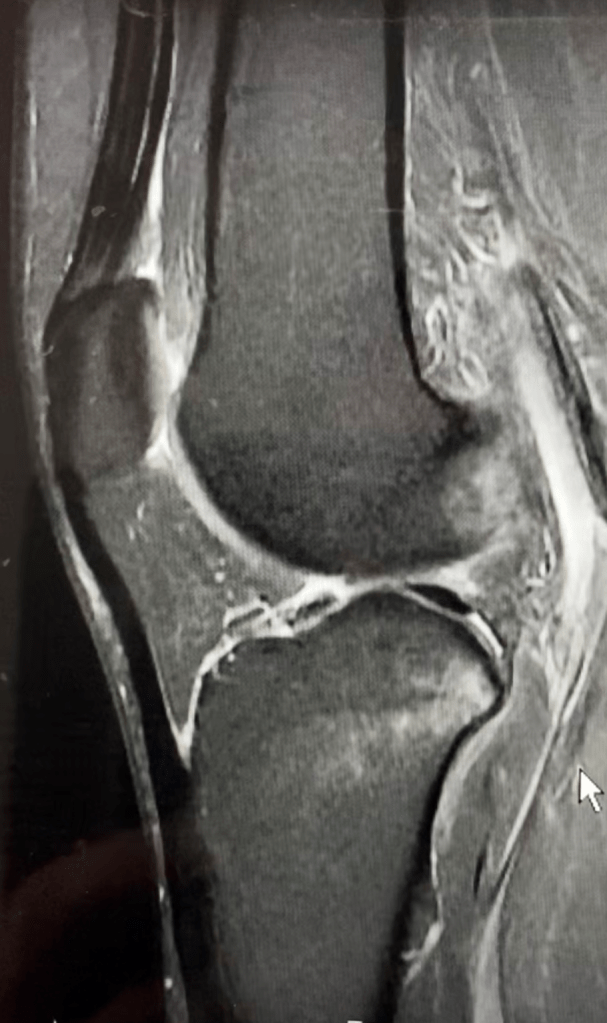

It was starting to get real, and I told the Dr. that I wanted to get the whole process started and put behind me as quickly as possible, since I had waited a beat with my shoulder dislocation, which made recovery much more dragged out. I was able to get an MRI later the same day, and the Dr. called to relay the findings. “Is it good news?” I asked anxiously, not really knowing how to start the conversation. “Yes,” was the reply. I had a femoral avulsion tear (the ligament is torn off the wall of the bone, see MRI images), and he could most likely perform a repair vs. a reconstruction, but it would be an interoperative decision. I had just finished reading the educational packet given to me at the ski resort clinic, figuring I should start being a good patient, and in the packet it said, and I quote, “The only way to fully fix a torn ACL is with surgery. Doctors rarely sew torn ACLs back together since this most often fails. Instead, doctors replace the ligament with a tendon from another part of the body or from a donor. This is called an ACL reconstruction.”

MRI IMAGES

Knowing what I know now, the Dr. was giving me good news, but I didn’t take it that way. “I just read that you can’t repair ACL’s, you have to reconstruct.” I then went into full blown second phase of grief, ANGER, and he did his best to talk me off the ledge. I couldn’t have been the first patient to react the way I did, is what I like to tell myself. The fact that my meniscus was fine didn’t offer much solace. To educate me further, he sent a few medical articles on ACL repair. My main takeaways after getting through the medical jargon were 1) there is drilling involved, 2) repair is not recommended for patients under 21, 3) there are several factors a surgeon will use to assess if repair is possible (tissue quality, location of tear, etc.), but mostly that there is drilling involved. Eek.